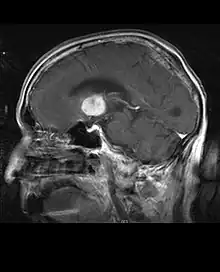

La tomodensitométrie (TDM) et L'imagerie par résonance magnétique (IRM) peuvent détecter efficacement une néoplasie dans le cerveau. L'IRM est plus sensible que la TDM pour identifier les lésions, mais présente des contre- indications pour les patients porteurs de stimulateurs cardiaques, de prothèses incompatibles, de clips métalliques et contre-indications. La TDM reste la méthode de choix pour détecter les calcifications au sein des lésions ou les érosions osseuses de la calotte ou de base du crâne. L'utilisation d' agents de contraste, iodés dans le cas du scanner et paramagnétiques (gadolinium) dans le cas de l'IRM, permet l'acquisition d'informations sur la vascularisation et l'intégrité de la barrière hémato-encéphalique, une meilleure définition de la tumeur tumorale par rapport à l' œdème environnant et à la génération d' hypothèses sur le degré de malignité. L'examen radiologique permet également d'évaluer les effets mécaniques et les modifications importantes des structures cérébrales résultant de la tumeur, telles que l' hydrocéphalie et les hernies, dont les effets peuvent être fatals. Enfin, en préparation à la chirurgie, ce diagnostic peut être utilisé pour déterminer la localisation de la lésion ou l'infiltration de la tumeur dans des zones vitales du cerveau. À cette fin, l'IRM est plus efficace que la tomodensitométrie car elle peut fournir des images en trois dimensions.

Sur-L'IRM montre une tumeur intracrânienne comme une lésion massive qui peut devenir plus luminescente après utilisation du produit de contraste. Cependant, il y a toujours une anomalie de signal dans -L'imagerie par résonance magnétique, qui indique la présence d'une néoplasie ou d'un œdème vasogénique. Habituellement, une luminescence accrue (amélioration du contraste) indique une tumeur d'un grade supérieur de malignité. Un anneau de contraste est caractéristique du glioblastome, avec la partie luminescente correspondant à la partie vitale de la tumeur maligne, et la plus foncée - zone hypointense correspondant à une nécrose tissulaire.

Glioblastome

Les tumeurs des cellules gliales les plus courantes et les plus malignes sont les glioblastomes. Ils consistent en une masse hétérogène de cellules d'astrocytome peu différenciées principalement chez l'adulte. Ils surviennent généralement dans les hémisphères cérébraux, plus rarement dans le tronc cérébral ou la moelle épinière. Sauf dans de très rares cas, comme toutes les tumeurs cérébrales, elles ne s'étendent pas au-delà des structures du système nerveux central.

Le glioblastome peut provenir d'une forme diffuse (II. grade) ou un astrocytome anaplasique (III. grade) développer. Dans ce dernier cas, il est dit secondaire. Cependant, lorsqu'elle survient sans antécédent ni signe de malignité antérieure, on parle de maladie primaire. Les glioblastomes sont traités par chirurgie, radiothérapie et chimiothérapie. Ils sont difficiles à guérir et rares sont les cas qui survivent au-delà de trois ans.

Les métastases cérébrales sont les néoplasmes intracrâniens les plus courants chez les adultes, étant dix fois plus fréquents que les tumeurs cérébrales primaires. Ils marchent à 20 jusqu'à 40 pour cent des adultes atteints de cancer et sont principalement associés au cancer du poumon et du sein et au mélanome . Ces lésions résultent de la propagation des cellules cancéreuses dans la circulation sanguine et surviennent le plus souvent à la jonction de la matière grise et blanche, où la section transversale des vaisseaux sanguins change, emprisonnant les embolies de cellules tumorales . 80 % des lésions surviennent dans les hémisphères cérébraux, 15 pour cent dans le cervelet et 5 pour cent dans le tronc cérébral. Environ 80 % des patients ont des antécédents de cancer systémique et 70 pour cent ont de multiples métastases cérébrales.

Des progrès significatifs ont récemment été réalisés dans le diagnostic et le traitement de ces lésions, entraînant une amélioration de la survie et du contrôle des symptômes. L'apparition des signes et des symptômes est similaire à celle d'autres lésions massives du cerveau. La méthode de diagnostic de choix est l'imagerie par résonance magnétique utilisant des produits de contraste.